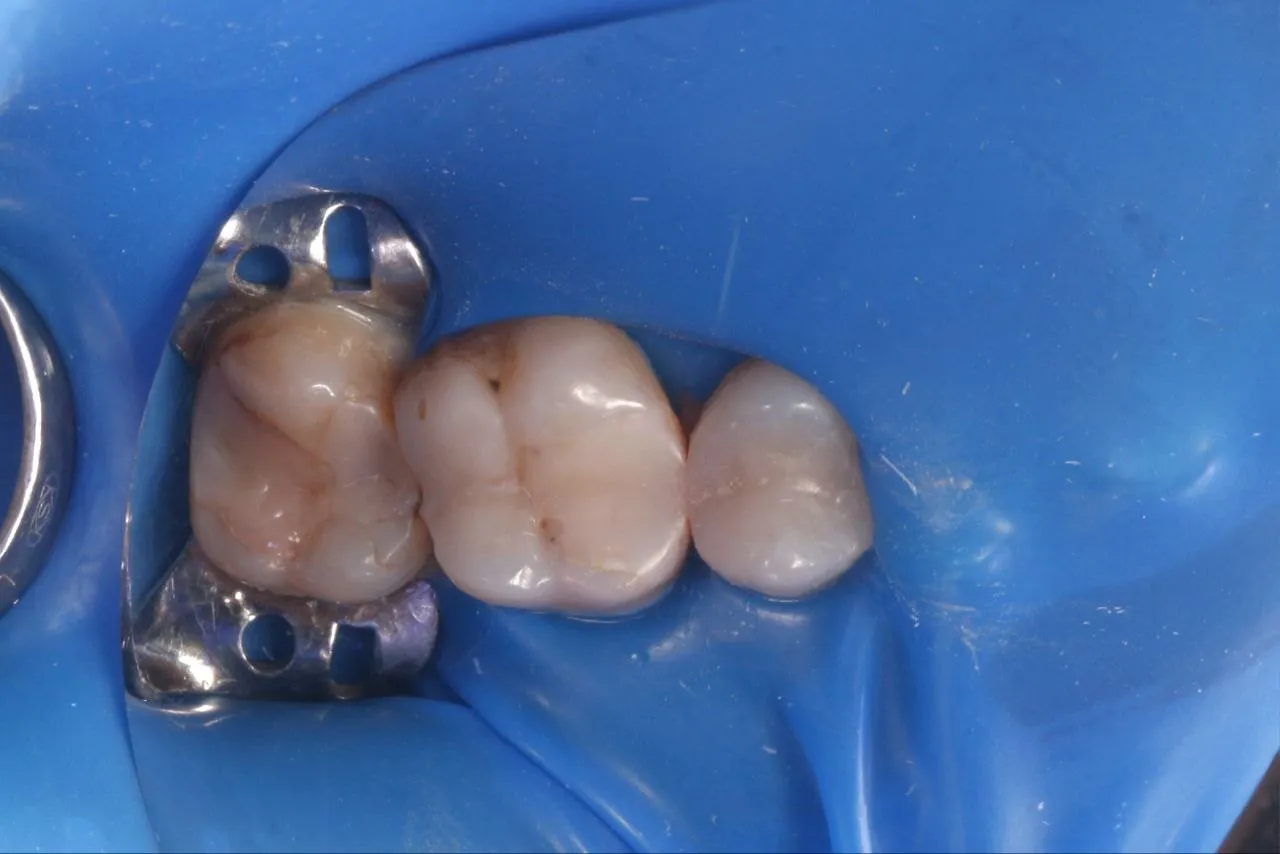

Лікування глибокого вторинного карієса зубів 17 та 16